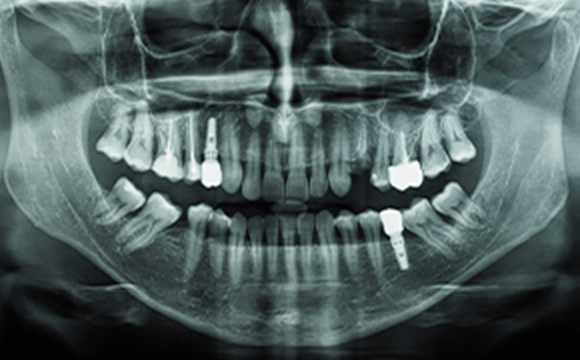

検査歯科用CTを用いた3次元立体画像で安全に埋入

血管・神経の位置、骨の状態を3次元画像で確認し、インプラントを埋入する位置、深さをCTで精緻に検査し、安全に手術を行います。

撮影された画像の例